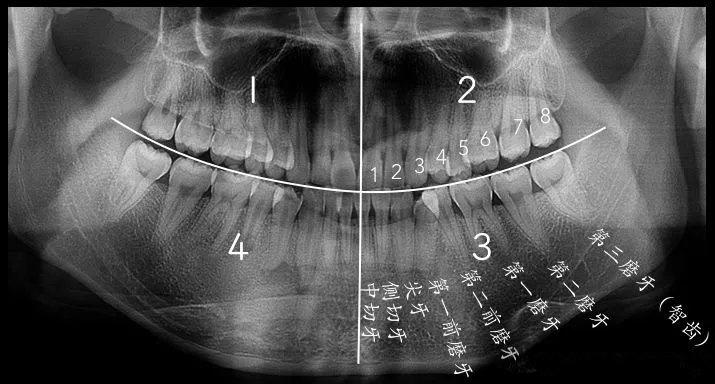

全景片怎麽(me) 看有無智齒

2、想要拔除智齒?先要到醫院拍個(ge) 全景片甚至是CT片,看看有沒有智齒,有幾顆智齒?全景片一兩(liang) 百元,CT片三四百元。然後再看智齒目前是否發炎,如果發炎需要先消炎再考慮拔除,消炎衝(chong) 洗等費用不確定,智齒拔牙目前一般在千多元左右比較正常。

5、牙齒不整齊,有虎牙、歪牙?一般需要先到醫院拍全景片、頭顱正位片和側(ce) 位片等,每個(ge) 價(jia) 格一般都在一百多左右,然後醫生會(hui) 給出大致的矯治方案,其實就是用哪種牙套好,價(jia) 格大致在多少錢左右。

6、牙齒缺了,做假牙?要先拍全景片,看看能不能種牙,缺了幾顆牙等等,醫生綜合評測後才能給出答案,目前一顆假牙費用是多少?活動假牙數百上千,烤瓷牙千多到幾千,種植牙上萬(wan) 到幾萬(wan) 的。然後就是看看自己喜歡哪種方式。